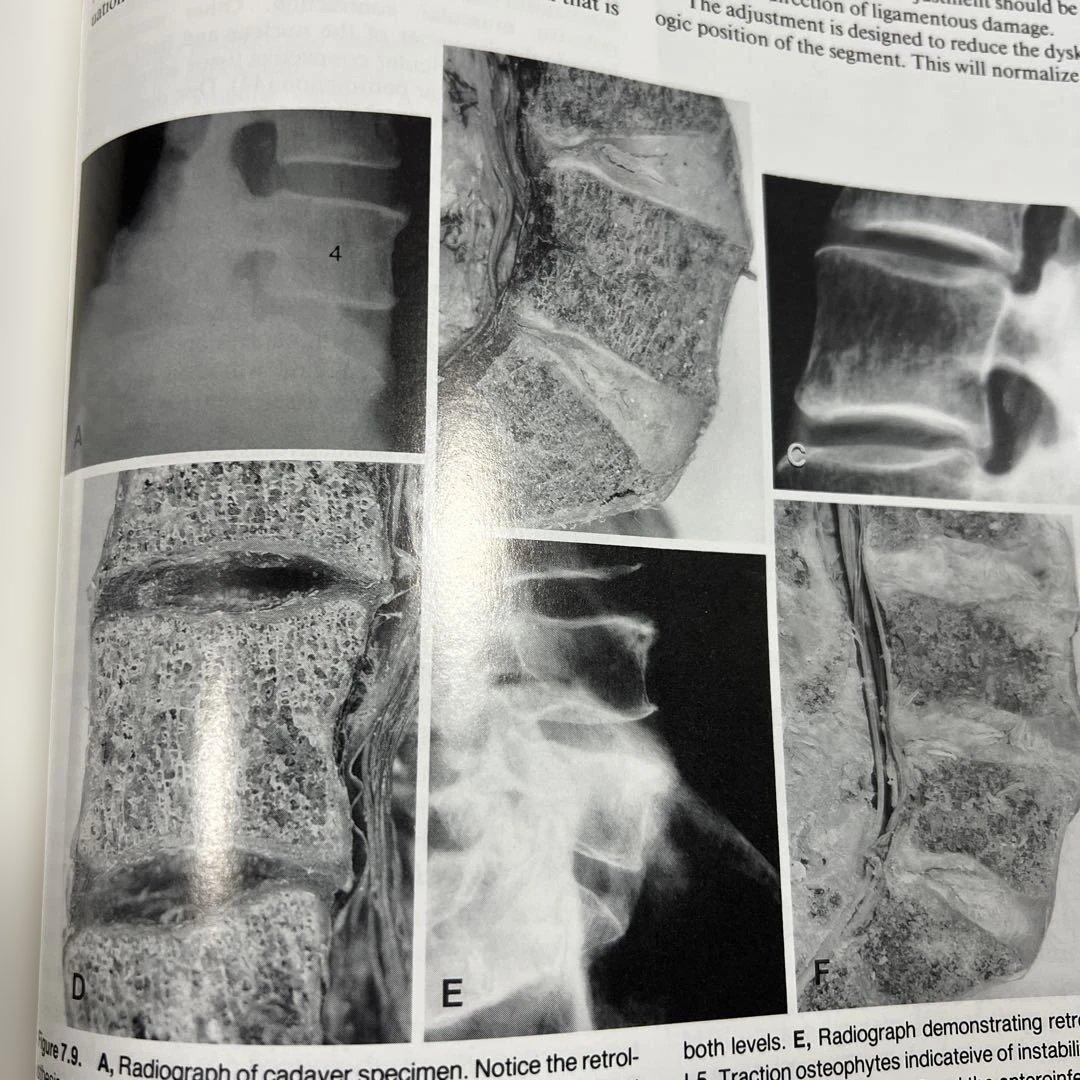

解剖学や神経診察に関する専門書のセット。(カイロプラクティック大学で使用される標準的な教本です。④- 書籍名: やさしい神経診察 定価¥3700①〜④までカバー後に治療院の名前と住所の押印があります。④以外には書き込み、線引きはありません。ご理解ご了承の上お求めいただければ幸いです。※裁断済み 犬の四肢と骨盤への整形外科アプローチ。まとめて4冊セットで①- 書籍名: ネッター解剖学図譜 第2版定価10000②- 書籍名: Textbook of Clinical Chiropractic (洋版)日本翻訳版は国内で発売されてましす。循環器疾患最新の治療 2026-2027 裁断済み!。看護管理学習テキスト 第3版 2021年版。)定価220ドル③- 書籍名: 動きの解剖学 II 定価 ¥6200 未読で備品です。骨盤輪・寛骨臼骨折治療実践マニュアル。●裁断済 非抜歯矯正治療 Molar Oriented Orthodontics。②には米国研修で指導していただいた先生からのメッセージがカバー後ろにあります。今日の治療薬2026 解説と便覧。操作法入門 DVD付き セット。④には蛍光ペンを使ったページが1ページあり。外科病理学 I & II セット 第4版。周術期の輸液・輸血療法 All in One。レビュー